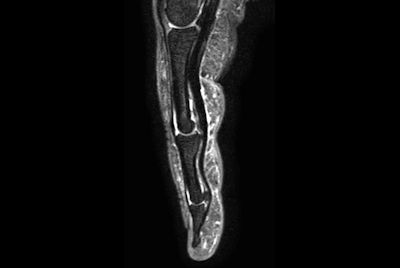

High resolution Ankle imaging in short scan times